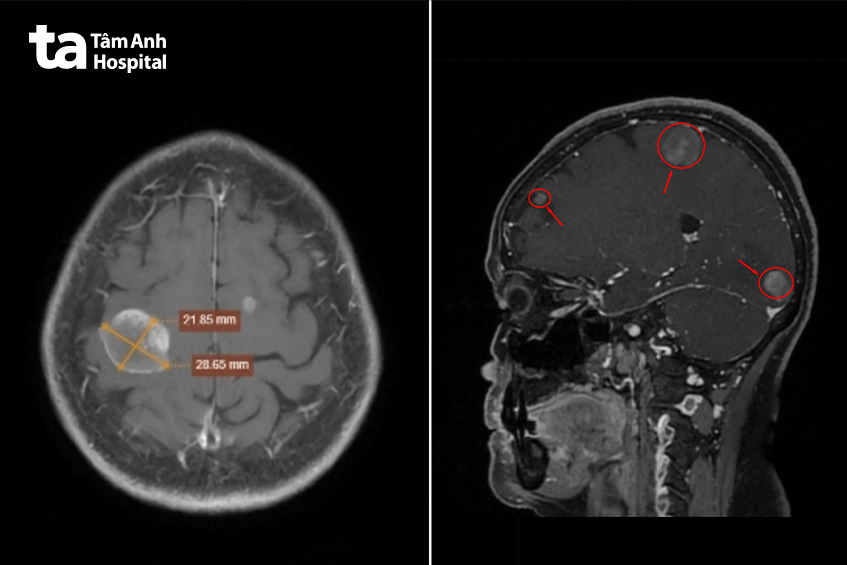

Kết quả MRI não phát hiện nhiều khối tổn thương kèm phù quanh tổn thương.

Theo BS.CKII Nguyễn Văn Phúc, Trưởng khoa Chẩn đoán hình ảnh Bệnh viện Đa khoa Tâm Anh TP.HCM (cơ sở P.Tân Hưng – Q.7 cũ), hình ảnh này gợi ý các khối u thứ phát, tức có thể di căn từ cơ quan khác trong cơ thể.

Một số khối có kích thước rõ, như khối ở thùy chẩm phải khoảng 18×19 mm và khối ở thùy đỉnh phải khoảng 21×28 mm. Tuy nhiên, cấu trúc não nhìn chung vẫn giữ vị trí bình thường, chưa ghi nhận dấu hiệu chèn ép đáng kể, phù hợp với việc người bệnh chưa xuất hiện triệu chứng thần kinh rõ ràng.